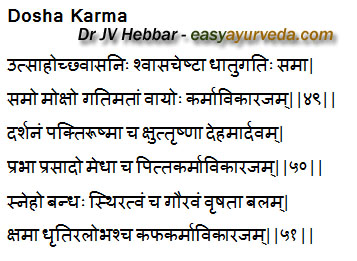

Functions of normal Doshas

Normal Functions of Vata Dosha –

When Vata is in its normal state, it reflects itself in the form of

Utsaha – enthusiasm,

Uchvasa – inspiration,

Nishvasa – expiration,

Cheshta – movements,

Vega Pravartana – expression of natural urges – like urination, etc.

Normal metabolic transformation of tissues and proper elimination of excreta.

Normal functions of Pitta Dosha –

Darshana – good vision,

Pakti – good digestion,

Ushma – normal temperature,

Kshut – normal hunger,

Trushna – thirst,

Mardava – bodily softness,

Prabha – lustre,

Prasaada – happiness and

Medha – intelligence.

Normal functions of Kapha Dosha –

Effects of Kapha in its normal state are

Sneha – unctuousness, oiliness,

Bandha – cohesion, compactness,

Sthiratva – steadiness,

Gaurava – heaviness,

Vrushata – virility,

Bala – strength,

Kshama – forbearance,

Dhruti – patience, good memory and retention power

Alobha – lack of greed [49-51]